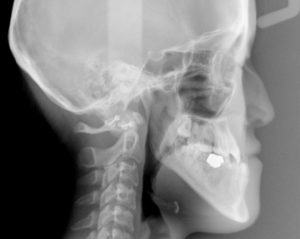

新着情報 0088初診時セファロ① – コピー Tweet 投稿日 : 2017年10月10日(火)カテゴリー : コメントを残す コメントをキャンセルメールアドレスが公開されることはありません。 * が付いている欄は必須項目ですコメント 名前 * メール * サイト 19歳 女性「手術をしないで 受け口を治したい」( 骨格的な反対咬合 ) ≫